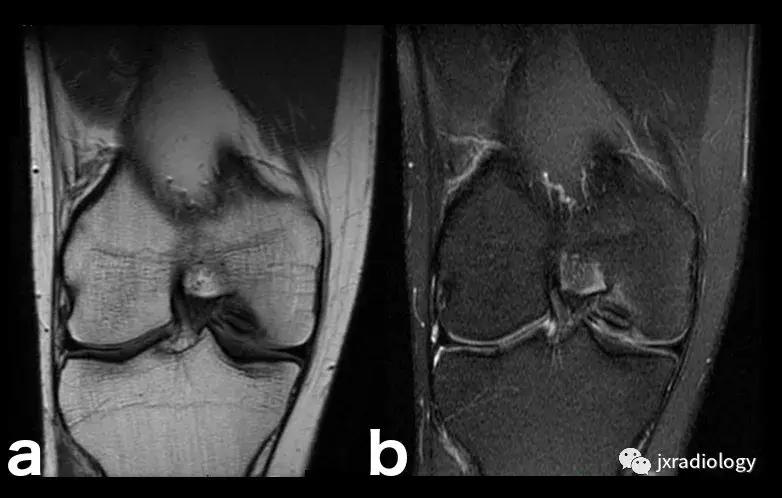

图18:剥脱性骨软骨炎(OCD)。OCD的病因学是未知的,可能是多因素的,包括损伤,血管因素,压力变化,发育差异和遗传学等。膝关节OCD最常见的部位是股骨内侧髁(75%)。这里显示了特征性的MRI表现,通常没有其它的损伤:在骨软骨碎片周围(b)有明显的小片骨髓水肿。(a,b:冠状T1-WI和冠状PD-FS-WI)。

图19:剥脱性骨软骨炎(OCD)。与图18相同的患者。X线片显示右侧股骨内侧髁见骨软骨碎片。